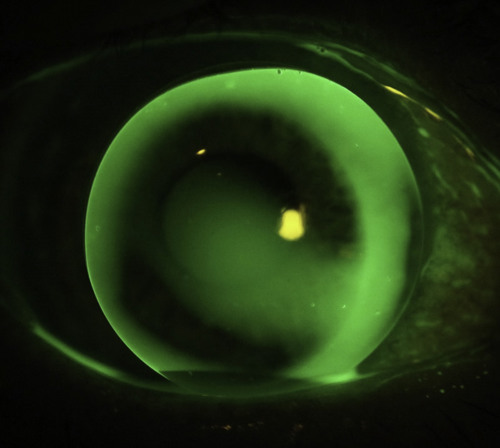

In the first instance, I always try to use corneal lenses with a material Dk of at least 100, because these designs maximise tear exchange and correctly fitted provide ample oxygen to meet the corneal graft demands in by far the majority of cases. I fit a relatively large lens, usually at least 10.4mm, trying to land the lens on the normal cornea outside the graft junction. The lens design needs to incorporate reverse geometry in flatter base curves to minimise pooling over the central cornea which is so often oblate (Fig 2).

Fig 2. This RGP lens needs a reverse geometry design to align the relatively flat graft curvature, courtesy of Paul Rose.